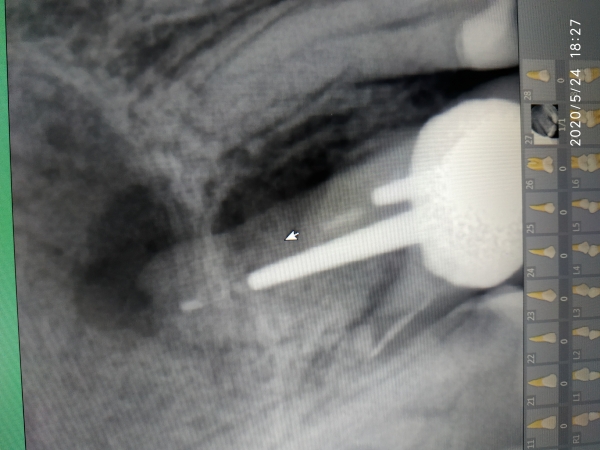

Сходила, сделала рентген. Врач сказал, что зуб нужно удалять.

Да, конечно, зуб необходимо удалить.